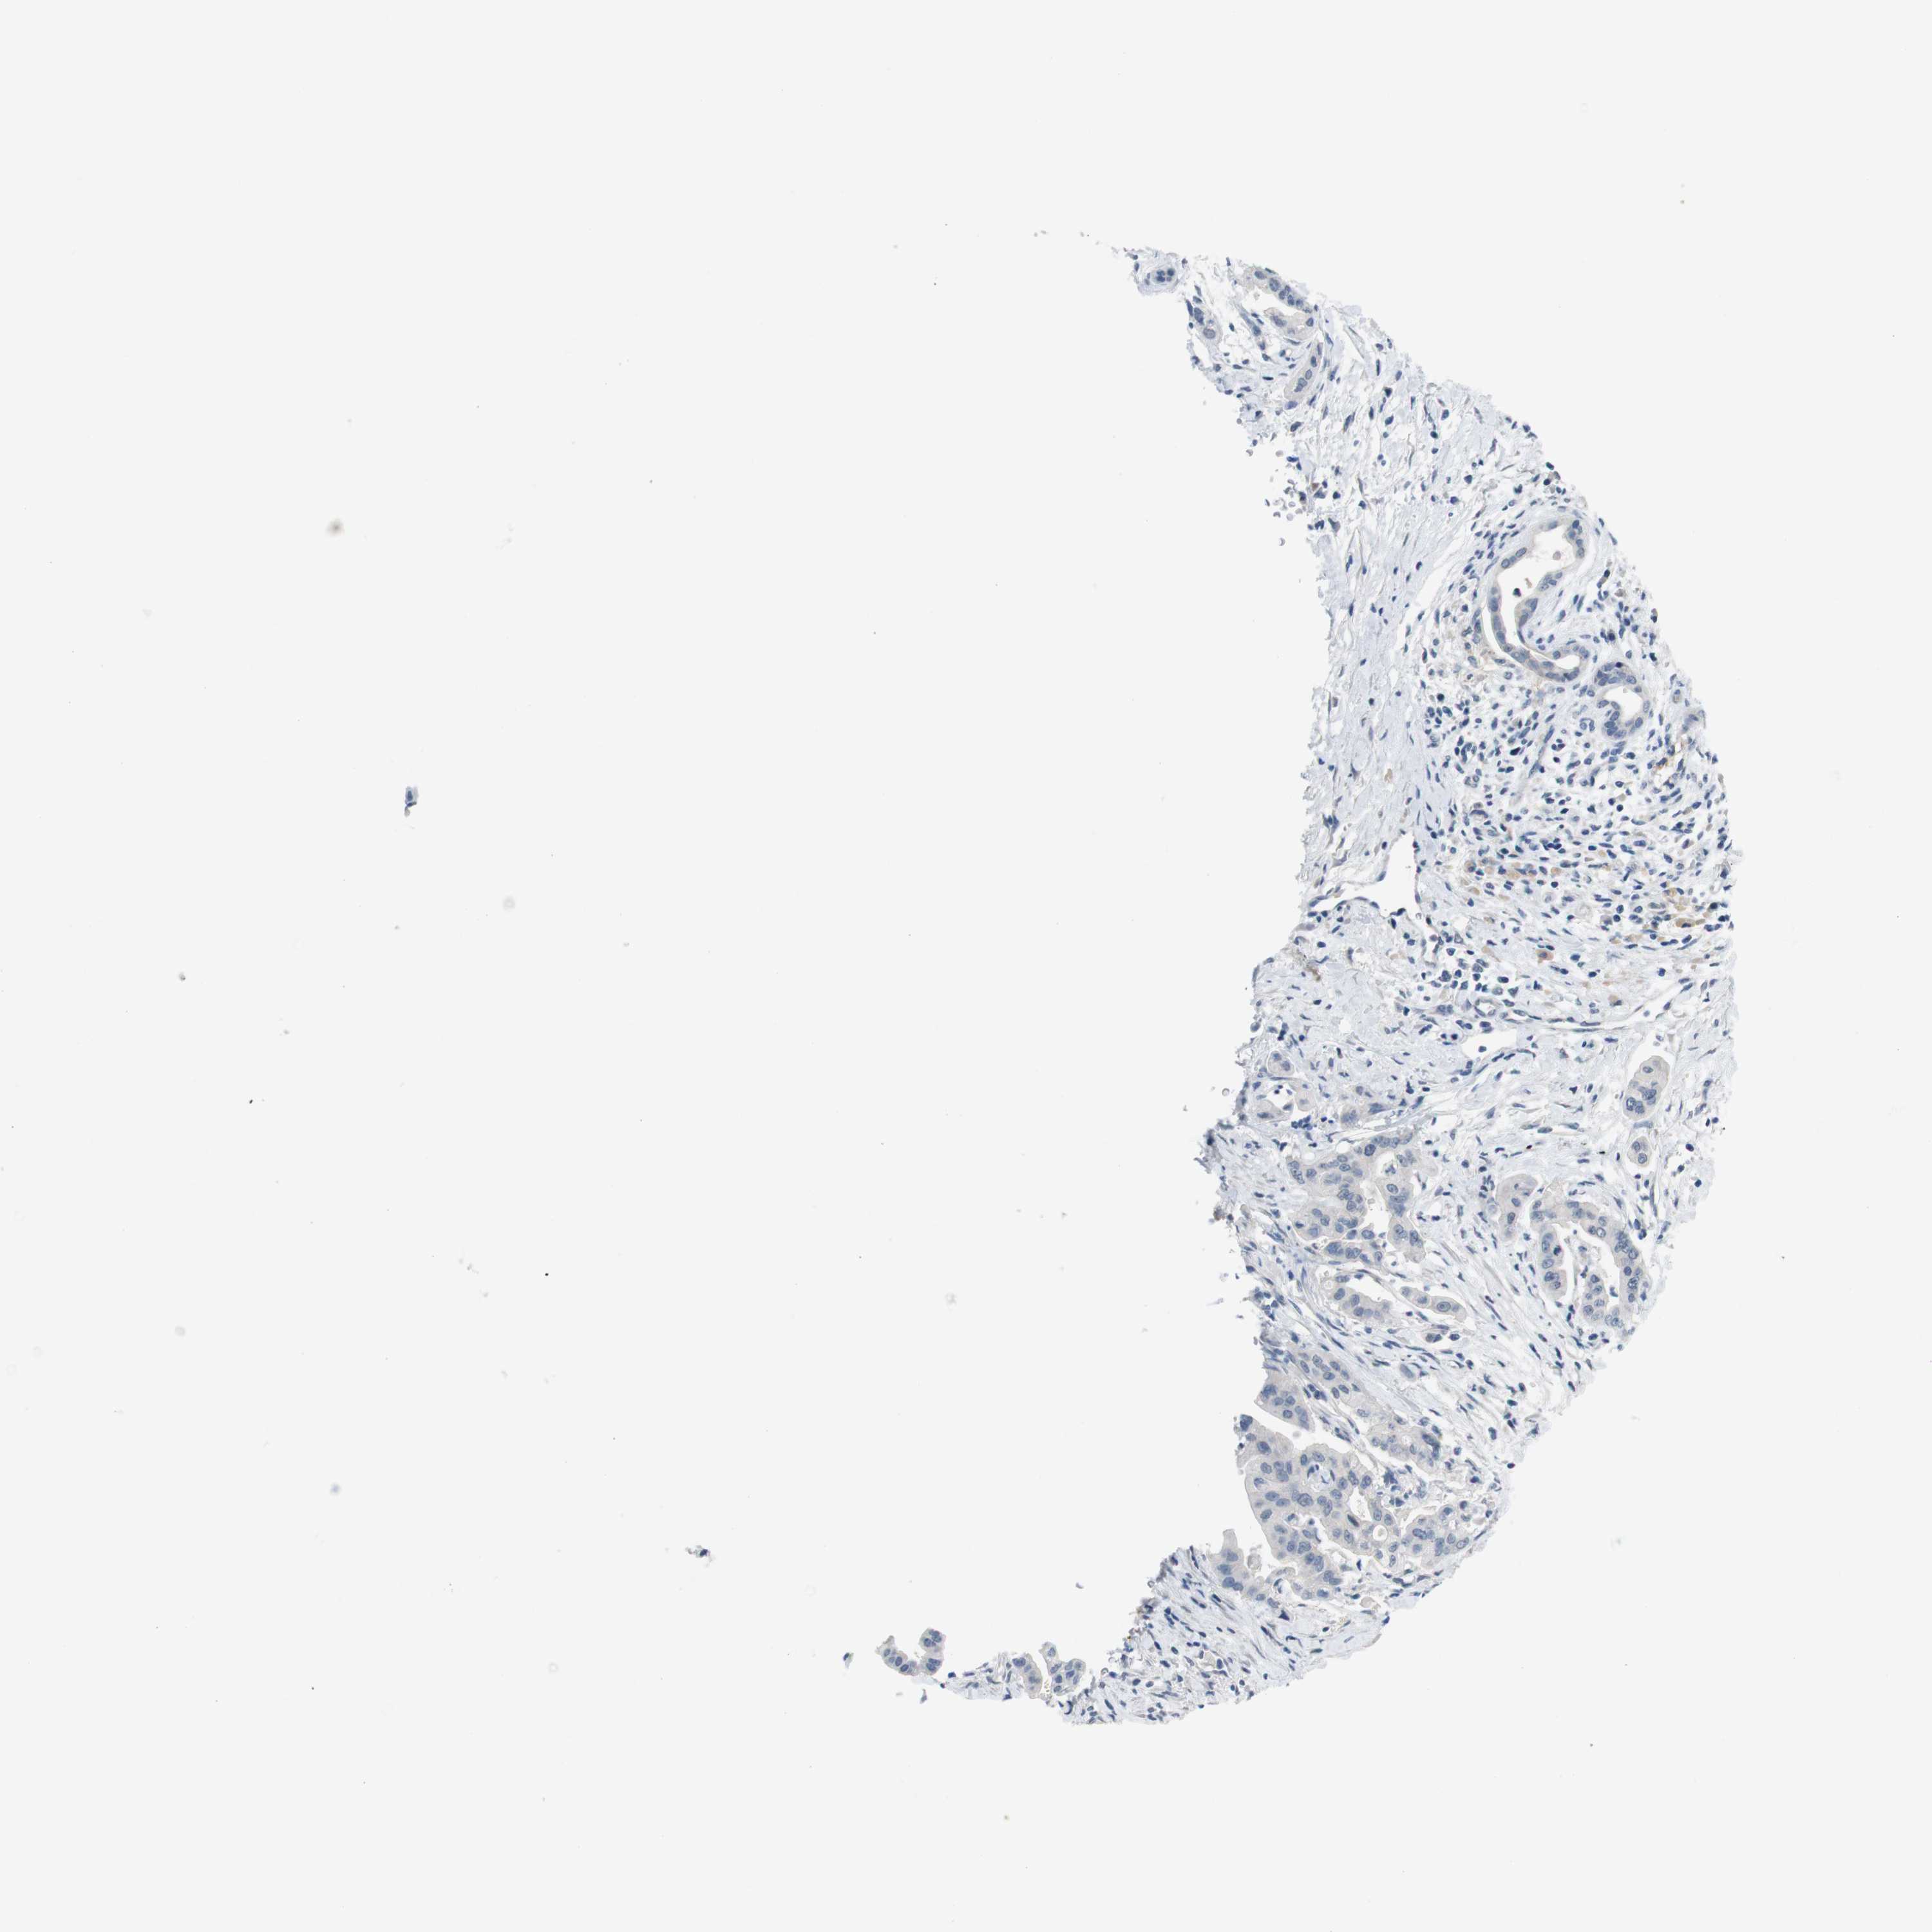

PANCREATIC CANCER - Protein expressioni

A mouse-over function shows sample information and annotation data. Click on an image to view it in a full screen mode. Samples can be filtered based on level of antibody staining by selecting one or several of the following categories: high, medium, low and not detected. The assay and annotation is described here.

Note that samples used for immunohistochemistry by the Human Protein Atlas do not correspond to samples in the TCGA dataset.

Antibody stainingi

Antibody staining in the annotated cell types in the current human tissue is reported as not detected, low, medium, or high, based on conventional immunohistochemistry profiling in selected tissues. This score is based on the combination of the staining intensity and fraction of stained cells.

Each image is clickable and will lead to virtual microscopy that enables deeper exploration of all samples and also displays staining intensity scores, fraction scores and subcellular localization as well as patient and tissue information for each sample.

Antibody HPA013770

Staining

High

Medium

Low

Not detected

Intensity

Strong

Moderate

Weak

Negative

Quantity

>75%

75%-25%

<25%

None

Location

Nuclear

Cytoplasmic/membranous

Cytoplasmic/membranous,nuclear

Adenocarcinoma, NOS

Adenocarcinoma, metastatic, NOS